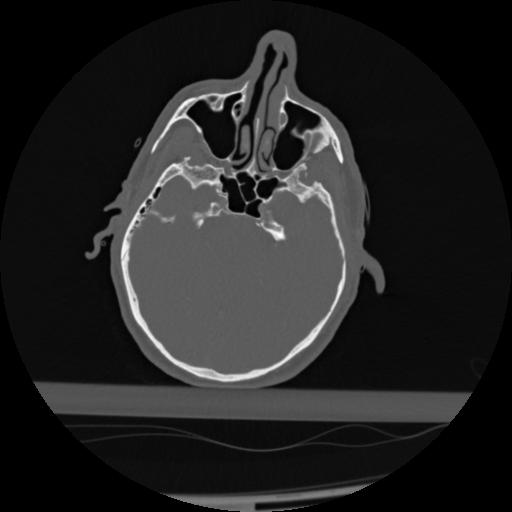

22 ANGIO,CE,Vol,0.5,ANGIO,,